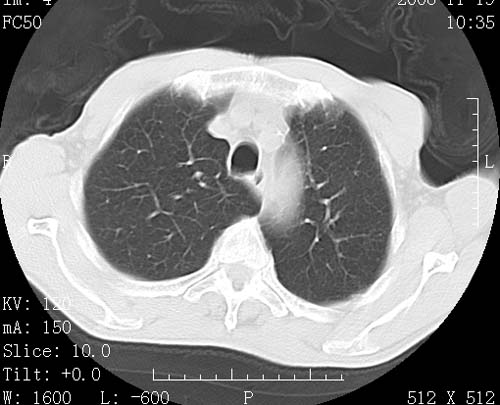

术前查体,双肺部结节是转移?结核?请点评

转移 隆突下淋巴结亦肿大

首先考虑转移,纵隔内淋巴结亦肿大;

1)符合食管癌表现。2)两肺及纵隔淋巴结多发性转移瘤。3)左肺上叶舌段及两肺下叶炎症感染。

食管癌伴双肺转移,评述:肺部毛细血管网丰富,全身血液均快速流经肺部,癌细胞容易过滤定植,形成转移瘤,影象特点为以毛细血管末梢为中心的结节灶,边缘光滑锐利,少见有中心空洞着,不同来源的转移瘤可有各自特点,如甲状腺癌为双肺弥漫性微结节,本例有原发灶,双肺影象灶典型,左肺舌段条带状网格样伴胸膜天幕征,可视为癌性淋巴管炎。